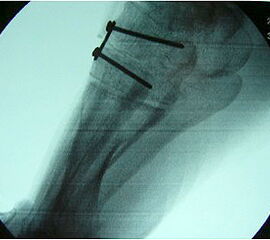

Radiologisches Beispiel einer fixierten Planovalgus Deformität Stadium III, 51 jähriger Patient. Stehendes präoperatives Röntgenbild und 1 Jahr postoperatives Röntgenbild des Fußes seitlich. Die Korrektur der Deformität umfaßte eine leicht korrigierende U

Abbildung 12

Im Stadium III der Tibialis posterior Sehneninsuffizienz bei fixierter Deformität und/oder erheblich eingeschränkter Inversion im USG aber stabilen und flexiblen Chopart-Gelenk und weniger als 10° fixierter Vorfußsupination eine in-situ oder leicht korrigierende USG-Arthrodese indiziert. Der Vorteil einer isolierten USG-Arthrodese gegenüber einer Triple- oder Double-Arthrodese ist die verbleibende, funktionell wichtige Beweglichkeit in der Chopart-Gelenkreihe. Um einem persistierenden fibulocalcanearem Impingement sicher vorzubeugen, sollte die USG-Arthrodese in maximal 5° Valgus- oder sogar Neutralposition erfolgen. Zur Prophylaxe eines Rezidivs wird die USG-Arthrodese zudem häufig mit einer medialisierende Tuber calcanei Osteotomie und / oder einem FDL-Transfer kombiniert (Abb. 12).